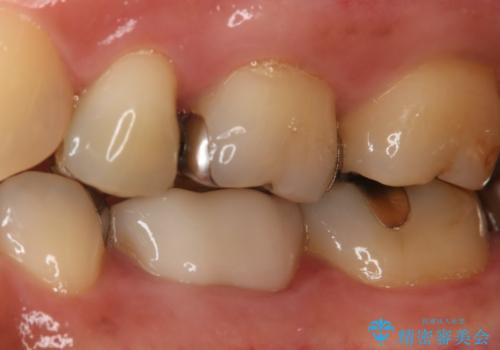

治療後は症状も無くなり経過は良好です。

セラミックでの治療を希望されたので、フルジルコニアクラウンでの治療を選択しました。